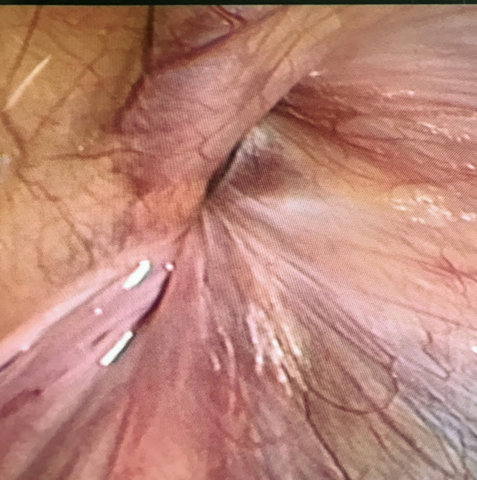

4. Rút chỉ, khâu buộc chỉ chôn dưới da. (Ảnh 3,4)

Ảnh 4: Lỗ bẹn sâu thu hẹp khi rút chỉ